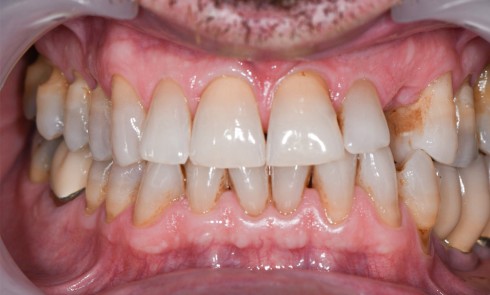

Résumé Ce rapport de cas pose la question des possibilités et des limites des bridges collés cantilevers postérieurs en céramique...